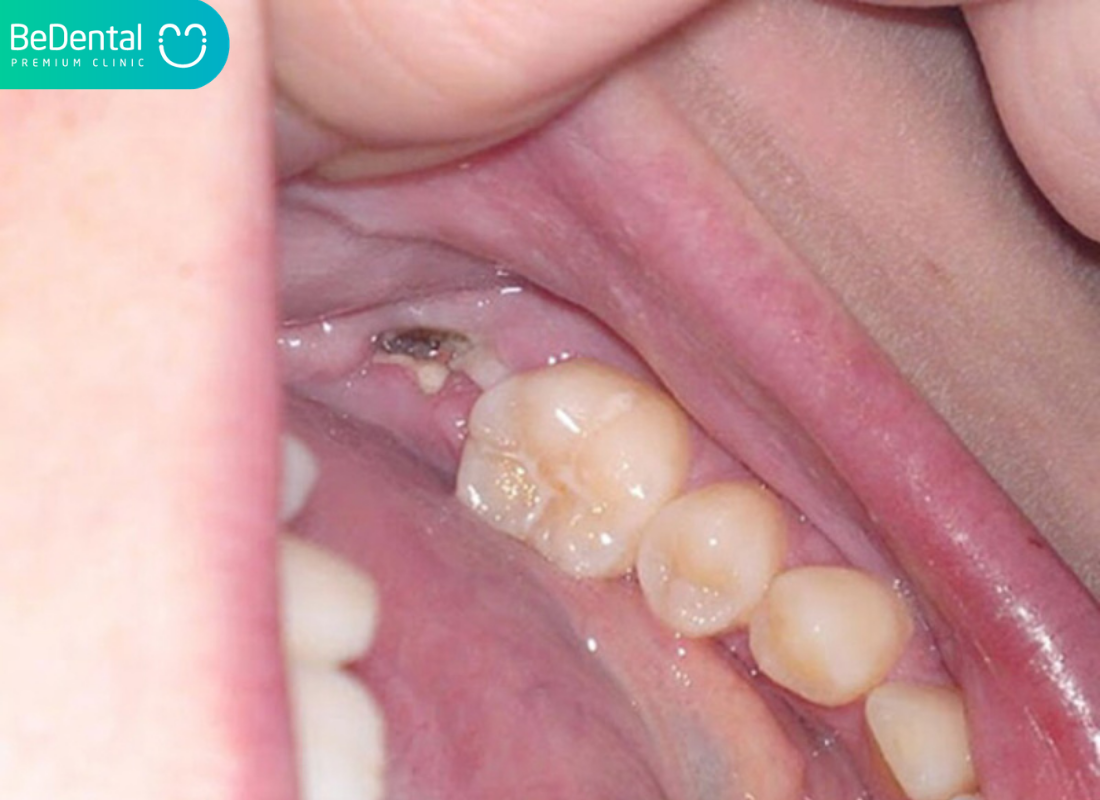

Tình trạng răng khôn bị lợi trùm (hay còn gọi là viêm lợi trùm răng khôn – Pericoronitis) là hiện tượng phần mô nướu bao phủ lên một phần hoặc toàn bộ bề mặt của chiếc răng hàm số 8. Thay vì mọc lên một cách thuận lợi và tách bạch khỏi nướu như các răng khác, chiếc răng này lại bị “mắc kẹt” dưới một lớp vạt nướu. Điều này tạo ra một khe hở giữa răng và nướu, biến nơi đây thành một “cái bẫy” chứa vụn thức ăn và vi khuẩn.

Phần nướu này không chỉ đơn thuần là che phủ mà còn có thể bị viêm nhiễm, sưng phồng do sự tấn công của vi khuẩn kỵ khí trú ngụ bên trong. Nếu không có sự can thiệp y khoa, mảng bám tích tụ dưới lợi trùm lên răng khôn sẽ dẫn đến hoại tử mô nướu hoặc gây hỏng chiếc răng bên cạnh.

Con người hiện đại có xu hướng xương hàm nhỏ dần theo quá trình tiến hóa, trong khi số lượng răng vẫn giữ nguyên. Khi răng số 8 mọc lên sau cùng, chúng thường không còn đủ “chỗ đứng”. Chính sự thiếu hụt không gian này khiến răng không thể trồi lên hoàn toàn, tạo điều kiện cho phần nướu phía trên bao phủ lấy mặt nhai, dẫn tới hiện tượng răng khôn bị lợi trùm.

Vị trí của răng khôn nằm ở sâu nhất trong khoang miệng, nơi mà bàn chải thông thường khó có thể tiếp cận một cách triệt để. Khi thức ăn dắt vào khe hở giữa răng và vạt nướu, chúng sẽ lên men và tạo ra các túi mủ. Vi khuẩn phát triển mạnh mẽ khiến vùng lợi tại đây sưng to hơn, tạo nên một vòng xoáy bệnh lý: nướu sưng càng to thì càng che lấp răng, và răng càng bị che lấp thì càng khó vệ sinh.